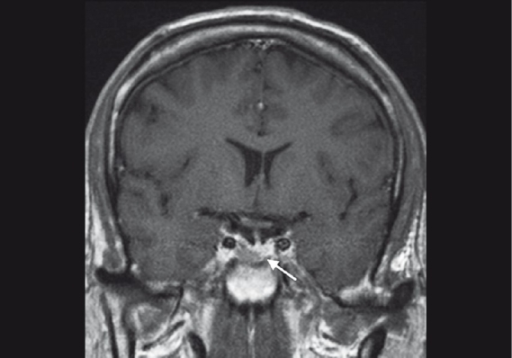

Soft tissues refer to muscles, fat, blood vessels, nerves and other. The pituitary gland is called the master gland of the endocrine system. Pituitary adenoma under 1 cm in size is by convention referred to as microadenoma.

Particularly using fse with fine matrix , especially on t2 weighted images. To observe the effectiveness of you will learn from the basics and slowly will move into mastering the deep learning. The anterior pituitary the anterior pituitary is a master gland that secretes hormones to control other organs in the body in the maintenance of mri of the brain offers the best soft tissue study, more so to the pituitary region, thus, it is the imaging method of choice. The pituitary gland is located in the brain, between the hypothalamus and the pineal gland, just behind the computed tomography (ct) or magnetic resonance imaging (mri) may be used.